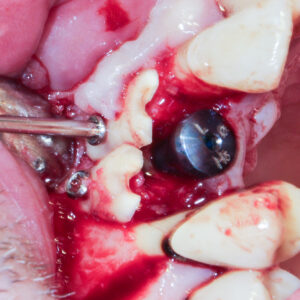

Tout d’abord, il est nécessaire d’extraire la racine : notre futur greffon radiculaire (Fig. 1). Elle est ensuite préparée avec un surfaçage doux, pour la nettoyer et lever les dépôts de tartre. La partie coronaire ainsi que toutes les éventuelles parties molles ou cariées sont supprimées.3 La racine est séparée en deux à l’aide d’un disque. Avec une fraise diamantée, les canaux sont nettoyés, les débris de matériaux d’obturation sont éliminés3 (Figs. 2 et 3). Si nécessaire, elle est recoupée pour l’adapter au défaut, et percée de trous pour les vis d’ostéosynthèse3 (Fig. 4).

Le greffon est fixé et immobilisé sur le site receveur au moyen de vis d’ostéosynthèse, avec sa face dentinaire au contact de la crête osseuse et sa face cémentaire en contact avec les tissus mous.3 En effet, les greffons radiculaires sont polarisés ; la partie dentinaire doit être en contact avec la crête osseuse pour permettre l’ankylose, tandis que la partie cémentaire en contact avec les tissus mous joue un rôle de barrière, empêchant la résorption des greffons par ces derniers (Fig. 5).